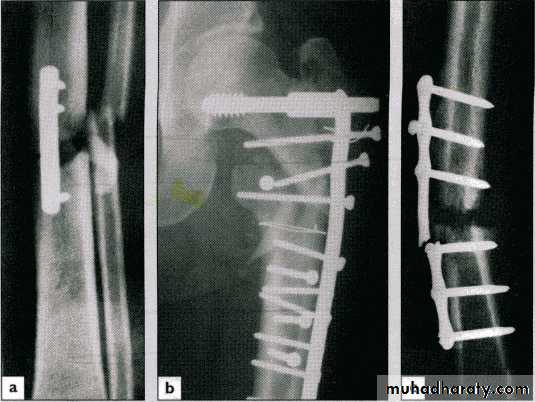

37External fixation

Screws (Schanz) pass above & below the # and are connected to an external frame

39Indications

Open #

Closed # with severe s.t. damage

Infected ## with bone loss (bone lengthening)

Pelvic fracturesAnaesthetic risk

Complications

Nerve & vessel injury

Screw loosening

Pin-track infection